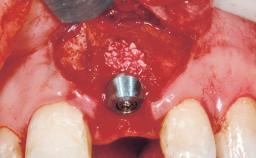

Late Flapless Placement of an Implant in a Maxillary Left Central Incisor Site

A 39-year-old male patient presented with a chief complaint of discomfort and gingival discoloration around his maxillary left central incisor. He was in good general health and was a non-smoker. His past dental history was significant because of the traumatic fracture of tooth 21 in a sporting accident at age 13. Initial dental treatment included endodontic therapy and a full-coverage restoration. The patient became symptomatic 5 years later, when structural failure of the tooth resulted in the dislodgment of the crown. Endodontic retreatment, apical surgery, and post-and-core restoration were performed.

Bone Augmentation Horizontal|Staged

Augmentation Materials Xenogenous|Membrane

Soft Tissue Grafting Simultaneous

Bone Volume Deficient horizontally, requiring prior grafting